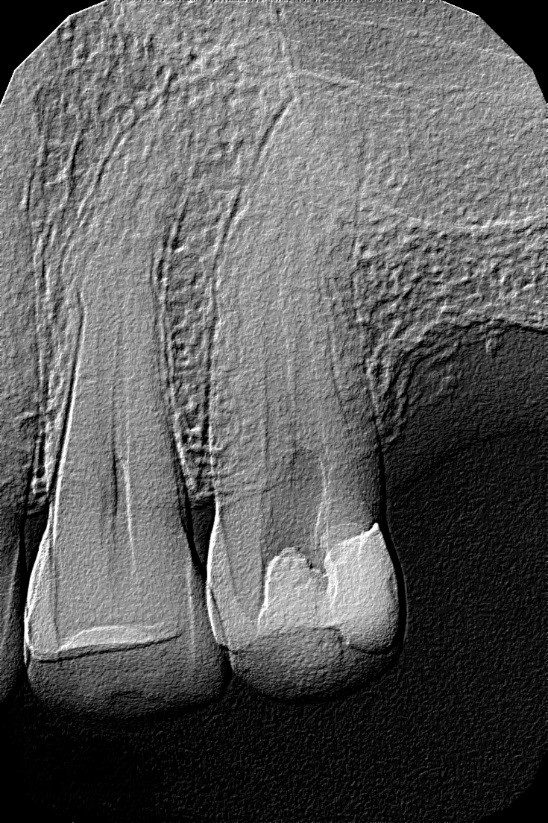

- Zdjęcia rentgenowskie – jak wcześniej wspomniano, zdjęcia rentgenowskie nie zawsze pozwalają na wykrycie niuansów budowy anatomicznej korzeni i kanałów. Przed podjęciem leczenia kanałowego należy jednak koniecznie zlecić wykonanie zdjęcia zębowego. Jeśli istnieje podejrzenie obecności kanału dodatkowego, to w niektórych sytuacjach można go uwidocznić dzięki wykonaniu drugiego zdjęcia tego samego zęba, ale w innej projekcji. Przesunięcie tubusu lampy rentgenowskiej o kilka stopni może odkryć przed endodontą nietypowo zlokalizowany kanał czy nawet „nadliczbowy”/rzadziej występujący korzeń. Należy przy tym pamiętać, że przed leczeniem kanałowym zaleca się wykonanie zdjęcia zębowego, a nie pantomograficznego. Według wytycznych Europejskiego Towarzystwa Endodontycznego na radiogramie należy uwidocznić cały kanał (kanały) oraz 3‑4 mm okolicy okołowierzchołkowej (3, 4, 5). Podczas radiologicznej oceny wewnętrznej anatomii zęba warto zwrócić uwagę na zjawisko „zanikania” światła kanału korzeniowego (ryc. 3, 4). Najczęściej nie jest to obliteracja, ale fakt podziału kanału na dwa, trzy lub nawet więcej węższych kanałów (4, 5).

Ryc. 3. Zdjęcie rentgenowskie zęba 44 przed leczeniem. Zanikanie światła kanału korzeniowego może świadczyć o rozdzielaniu się kanału.

Źródło: Olczak K, Pawlicka H. Zastosowanie rentgenodiagnostyki w endodoncji. Mag Stomatol. 2015; 7-8: 32.

Ryc. 4. Zdjęcie rentgenowskie zęba 44 uwidacznia prawidłowe wypełnienie kanałów.